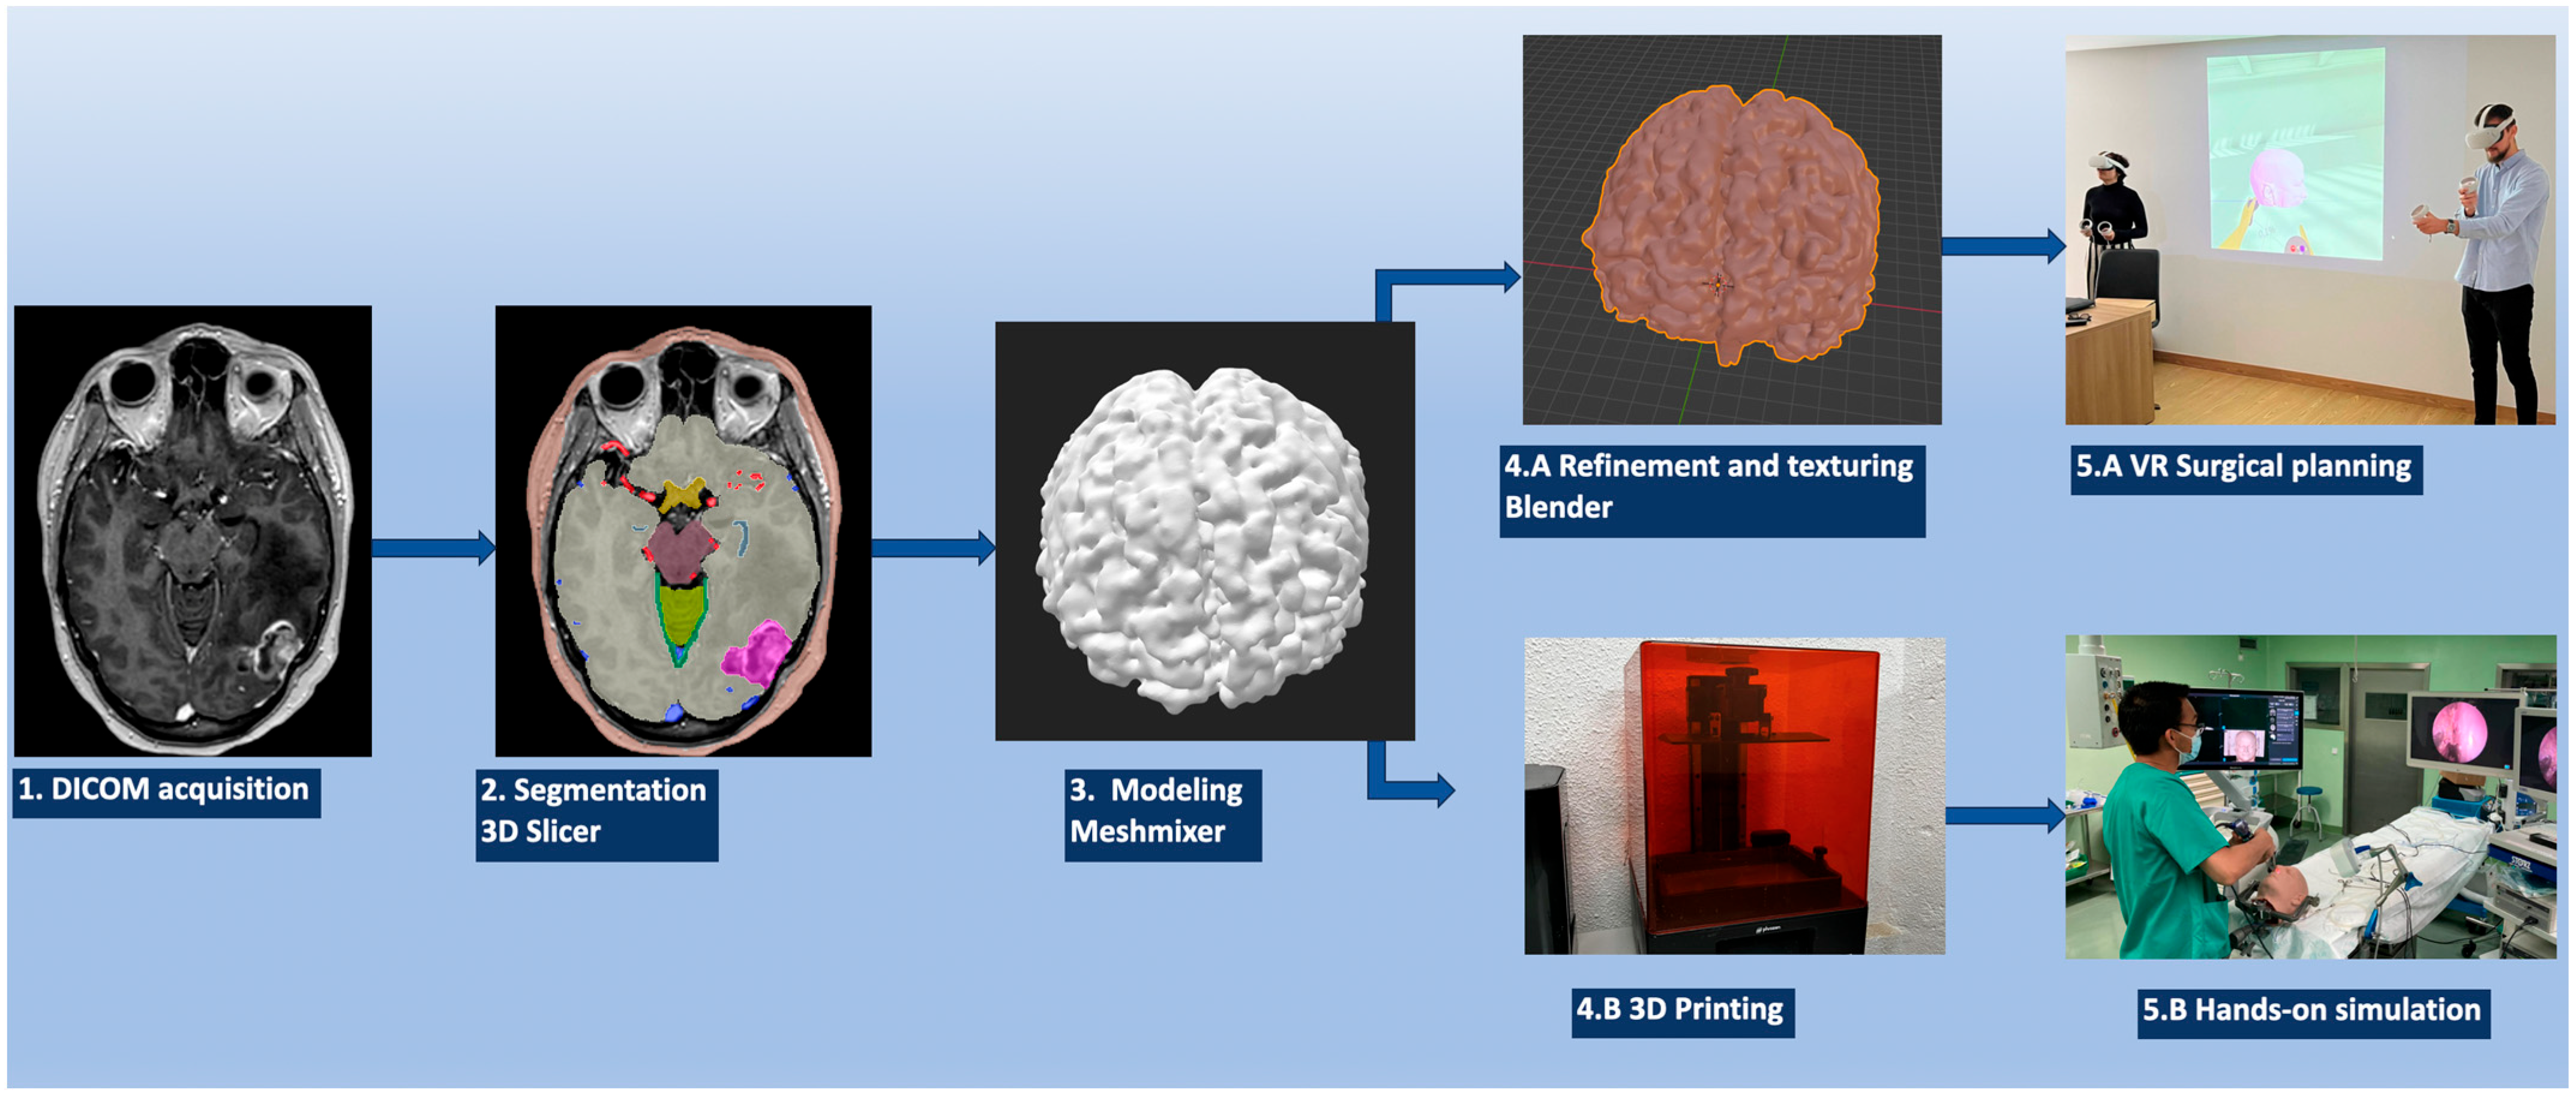

2. Materials and Methods

2.1. Image Data Acquisition

2.2. Object Segmentation

2.3. Sculpting the 3D Objects

2.4. VR/AR Implementation

2.5. 3D Printing